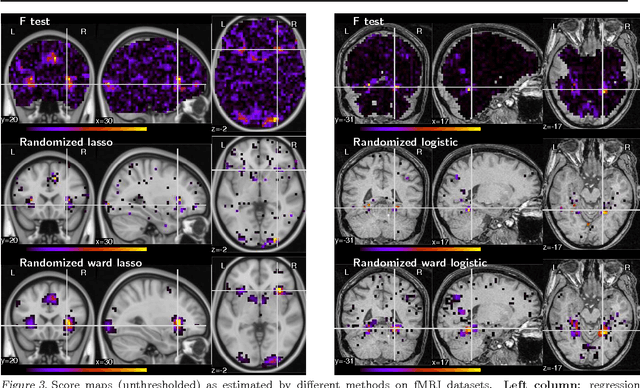

Functional neuroimaging can measure the brain?s response to an external stimulus. It is used to perform brain mapping: identifying from these observations the brain regions involved. This problem can be cast into a linear supervised learning task where the neuroimaging data are used as predictors for the stimulus. Brain mapping is then seen as a support recovery problem. On functional MRI (fMRI) data, this problem is particularly challenging as i) the number of samples is small due to limited acquisition time and ii) the variables are strongly correlated. We propose to overcome these difficulties using sparse regression models over new variables obtained by clustering of the original variables. The use of randomization techniques, e.g. bootstrap samples, and clustering of the variables improves the recovery properties of sparse methods. We demonstrate the benefit of our approach on an extensive simulation study as well as two fMRI datasets.